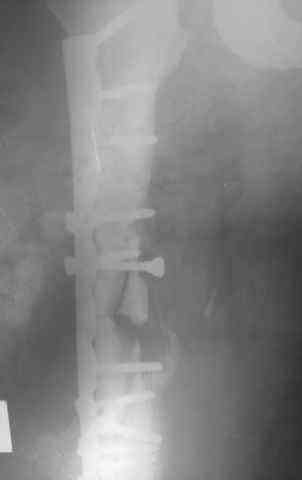

[Ortho] Несрошийся открытый фрагментарный,оскольчатый,перелом в/с/3 правого бедра

Несрошийся открытый     фрагментарный,оскольчатый,перелом в/с/3 правого бедра с размозжением мягких тканей.

Операция:16.12.09,открытый накостный МОС,аутокостная пластика(из крыла подвздошной кости)правого

бедра.После п/о периоде заживление раны вторичным натяжением(на 5-е

сутки распущены швы, после очищения раны наложины вторичные швы)

На этапных RO-гр:остеолизис костного трансплантата и дистального фрагмента перелома

бедра.

Вопрос: дальнейшая тактика лечения - БИОС аутокостная пластика

(трансплантат на сосудистой ножке М/Б кости). Билокальный остеосинтез

по Илизарову с остеотомией подвертельной и надмыщелковой области бедра.